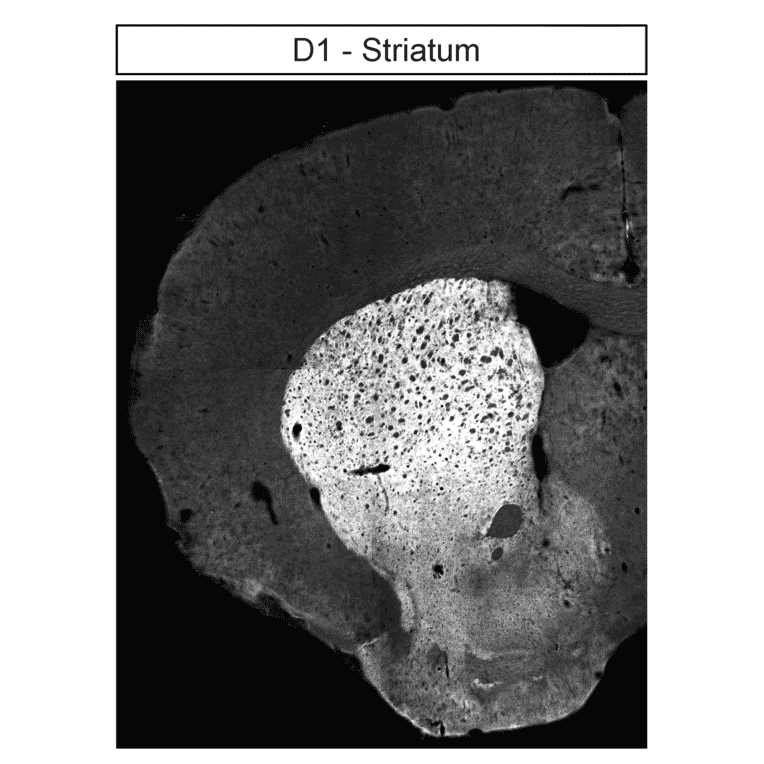

Localization of Dopamine Receptor 1 (DRD1) and Dopamine Receptor 2 (DRD2) in striatum by immunohistochemistry. Striatal sections were dewaxed, microwaved in citric acid, and incubated with either anti-DRD1 antibody (A334475) at 1:100 (left panel) or anti-DRD2 antibody (A334504) at 1:100 (right panel), followed by biotinylated anti-rabbit IgG and avidin-biotin solution. Color was developed with 3-amino-9-ethylcarbazole (AEC), and sections were counterstained with hematoxylin.